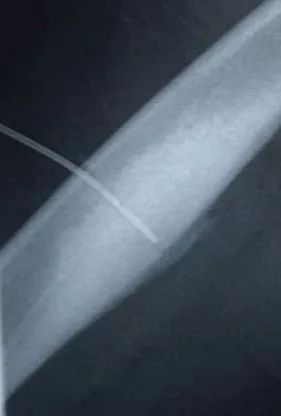

术中,劳永锵及潘海文凭借精湛的技术及丰富的手术经验,不断调整穿刺方向,精准直达病灶。在医疗设备科、麻醉科、放射科等各学科的配合,手术顺利完成。

此为横切面视角

术中,影像引导射频穿刺